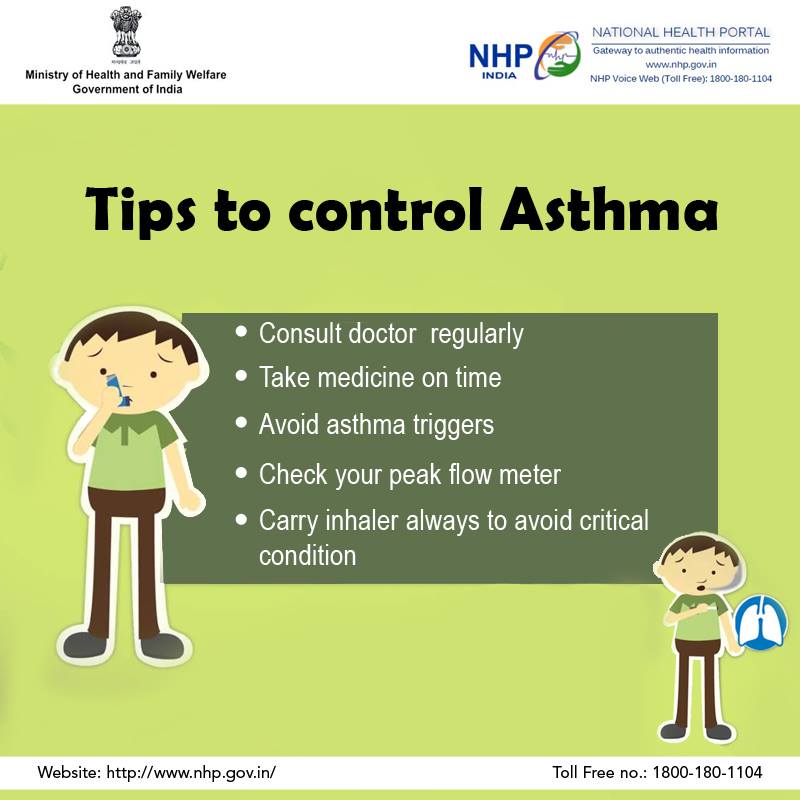

Learn about the different tips to control

#Asthma. For more updates, visit: http://bit.ly/2AeclL0#SwasthaBharat#AsthmaAwarenesspic.twitter.com/DVnMFCfBN4 ಧನ್ಯವಾದಗಳು. Twitter ಇದನ್ನು ನಿಮ್ಮ ಕಾಲರೇಖೆಯನ್ನು ಉತ್ತಮಗೊಳಿಸಲು ಬಳಸುತ್ತದೆ. ರದ್ದುಗೊಳಿಸುರದ್ದುಗೊಳಿಸು